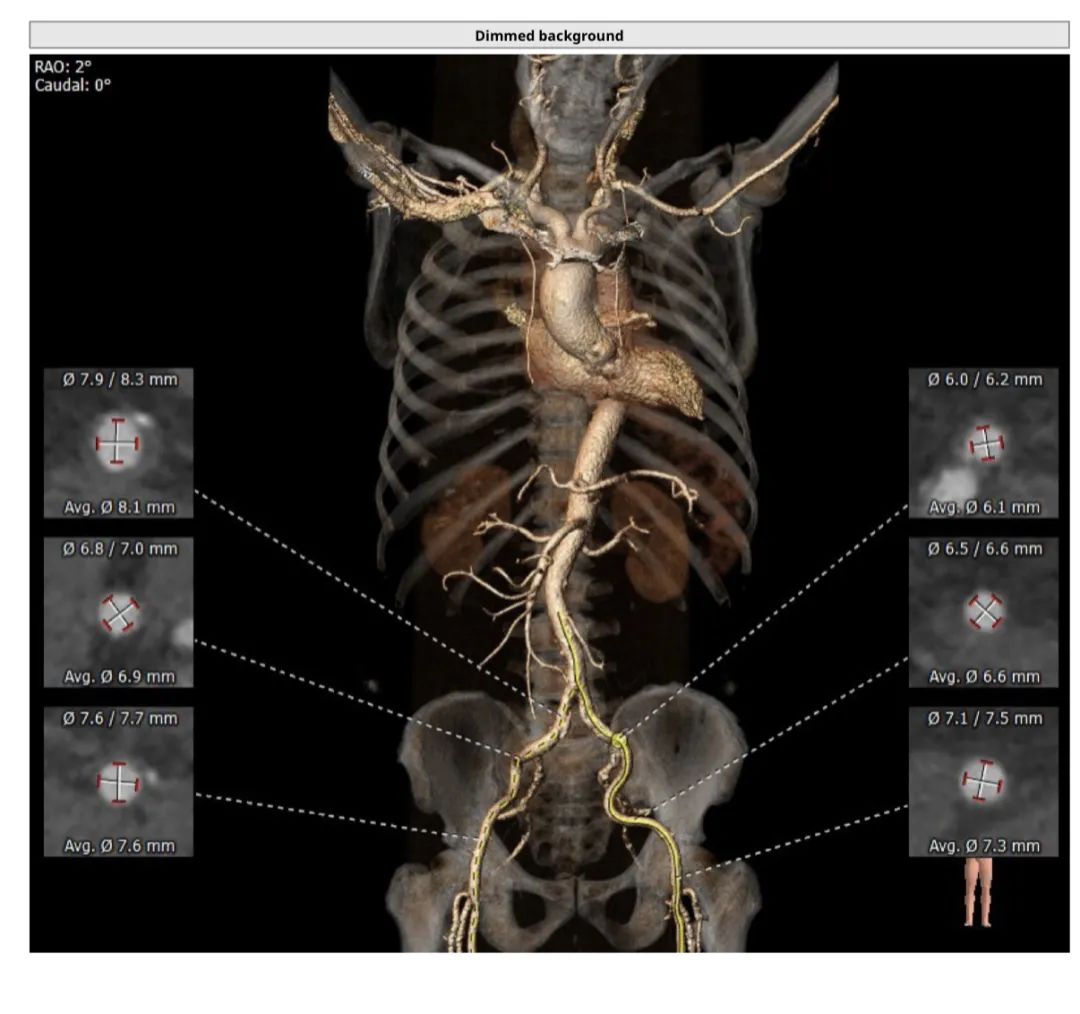

患者为功能型二叶瓣,中度钙化,瓣叶长且明显增厚,右冠高度16.5mm高度尚可,左冠高度10.5mm,左冠高度较低,且自体瓣叶冗长,评估冠脉风险较高。选择右股作为主入路。经过分析讨论,术者团队决定选择VenusA-Plus可回收输送系统,在瓣膜植入前,通过22mm球囊预扩张,确认瓣膜型号,同时评估瓣叶形态对冠脉开口的影响。

CT评估

冠脉情况

入路评估